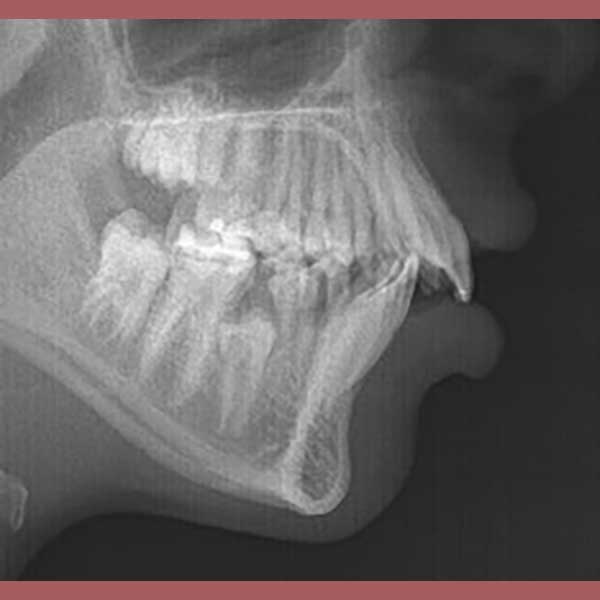

BEFORE

Protruded upper anteriors – fixed metal braces

After examining the case, I found that the upper of her front teeth were 8 mm of her lower front teeth, which is a large distance (normal to be 1 to 2 mm). The parents refused the option of tooth extraction, because of her young age, so I solved the problem without extraction because the main problem was caused by the retraction of the lower jaw I fixed it simply with a functional device